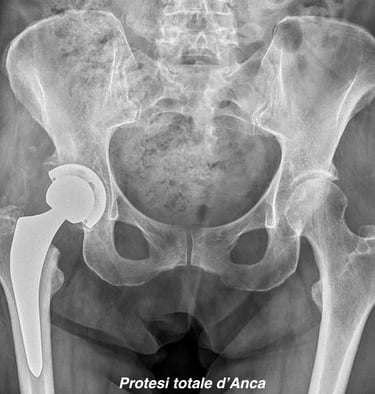

Chirurgia protesica d'anca

Impianti primari con tecnica mininvasiva ("HEROS approach")